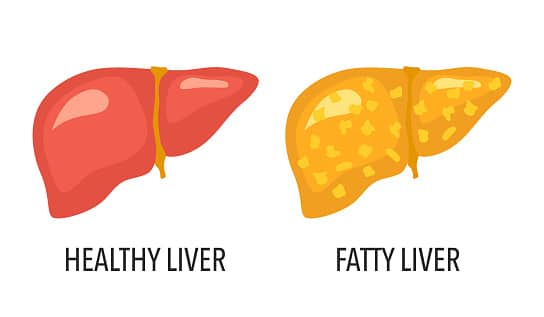

Η NAFLD, όπως λέγεται εν συντομία, αυξάνεται ραγδαία λόγω των αυξανόμενων ποσοστών παχυσαρκίας, σημείωσαν οι ερευνητές. Εξέτασαν 11 μακροπρόθεσμες μελέτες από πέντε χώρες (Ηνωμένες Πολιτείες, Ηνωμένο Βασίλειο, Νότια Κορέα, Σουηδία και Φινλανδία) που δημοσιεύτηκαν έως τον Μάρτιο του 2022. Μελέτησαν τη σχέση μεταξύ αυτού του τύπου ηπατικής νόσου και καρδιακής ανεπάρκειας σε περισσότερα από 11 εκατομμύρια ενήλικες μέσης ηλικίας.

Οι μισοί συμμετέχοντες ήταν γυναίκες, με μέση ηλικία τα 55 έτη και μέσο ΔΜΣ (δείκτης μάζας σώματος) 26, που θεωρείται ότι κάποιος είναι υπέρβαρος αλλά όχι άτομο παχυσαρκία. Οι ερευνητές διαπίστωσαν ότι περίπου το 26%, ή 2,9 εκατομμύρια συμμετέχοντες στη μελέτη, είχαν ήδη μη αλκοολική λιπώδη νόσο του ήπατος. Ο Δρ Alessandro Mantovani, του Τμήματος Ιατρικής του Πανεπιστημίου της Βερόνας στην Ιταλία, ηγήθηκε της έρευνας. Κατά τη διάρκεια της μέσης 10ετούς περιόδου παρακολούθησης, περισσότερα από 97.000 άτομα διαγνώστηκαν με καρδιακή ανεπάρκεια.

Η παρουσία NAFLD συσχετίστηκε με 50% αυξημένο κίνδυνο εμφάνισης καρδιακής ανεπάρκειας την επόμενη δεκαετία, ανεξάρτητα από ηλικία, φύλο, σωματικό λίπος, διαβήτη, υψηλή αρτηριακή πίεση, εθνικότητα και άλλους κοινούς παράγοντες καρδιαγγειακού κινδύνου. Ο κίνδυνος καρδιακής νόσου φάνηκε επίσης να είναι παράλληλος με τη σοβαρότητα της ηπατικής νόσου, ειδικά με την πιο εκτεταμένη ηπατική ίνωση (ουλές), σύμφωνα με τη μελέτη, όπου άγγιζε το 76%.